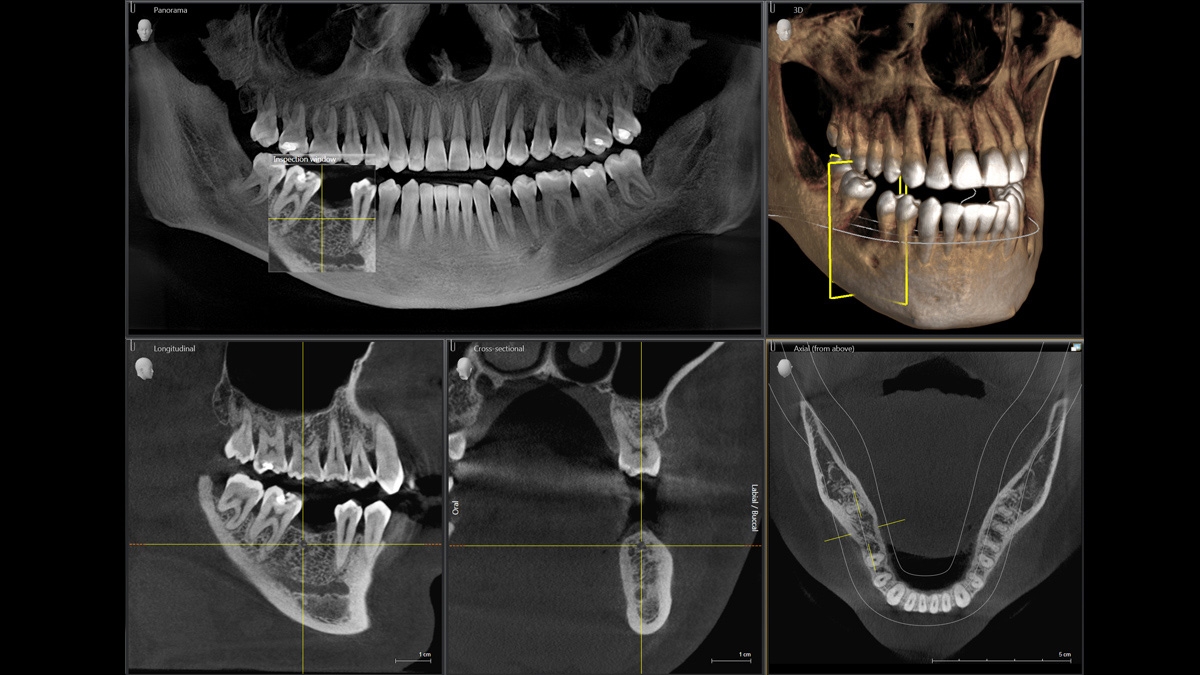

Диагностика последнего поколения, идеально решающая задачи рентгеновского обследования независимо от размеров клиники. Поля изображения зависят от определенной клинической картины, поэтому специалистам так удобно работать с ORTHOPHOS SL 3D. Данная установка делает объёмные картинки для одиночной реставрации в 3D качестве полностью всей челюсти такого размера, которого требуется.

Датчик DCS служит для выставления резкости снимков, причём его технологические особенности можно считать революционными для современного рынка стоматологического оборудования.

Чтобы предприятие функционировало «как часы», не последнюю роль играют такие факторы, как экономичность и продуктивность. Среди достоинств ORTHOPHOS SL 3D – возможность зафиксировать голову в трёх точках, что повышает комфортность не только работы врача, но и пациента; световые центраторы, накусочная окклюзионная пластина по запатентованной технологии; сенсорная панель Easypad; специальное ПО SIDEXIS 4.

ОБЪЁМ ДЛЯ ЛЮБЫХ ЦЕЛЕЙ

Планирование одиночной реставрации, эндодонтические исследования и пр. – для этого специалист может выбрать объёмные варианты 8 х 8 см или 11 х 10 см, также предлагается объём 5 х 5,5 см. Снимки в HD-качестве, стандартные настройки или выбор объёма обследования в зависимости от диагноза — всё это врач получает в отличном качестве, а для пациента излучение в районе исследования минимально.

Датчик прямого преобразования DCS

Конструктивные особенности датчика DCS заключаются в превращении рентгеновского излучения в электрическую энергию. Обычная для таких случаев промежуточная стадия светового луча отсутствует. Другими словами, значительно снизив потери сигнала, производитель максимально улучшил чёткость.

С технологией SL можно за один сеанс получить огромное количество снимков. Те из них, где фокусировка наиболее чёткая, автоматически соединяются. В итоге одна процедура — снимки челюсти полностью в самом лучшем качестве. Даже нестандартные случаи не станут помехой в обследовании. К примеру, при ретинированных зубах уже после того, как снимок сделан, нужную область можно выделить подробнее, и в ещё одном рентгене необходимость отпадает.

Программное наполнение для работы с изображениями с модулем MARS*

Металлические элементы в ротовой полости могут привести к возникновению помех на снимке. Благодаря наличию программного обеспечения MARS наличие объектов из металла определяется автоматически, влияние артефактов нивелируется. Таким образом не требуется повторного изображения для уточнения диагноза.

Модернизированный сенсорный экран Easypad с понятным и удобным интерфейсом позволяет выставить наилучшие параметры контрастности и разрешения. Систематизация данных по диагностике становится значительно удобнее и проще с ПО обработки изображений SIDEXIS 4, ORTHOPHOS.

1. Двух-и трёхмерные снимки совмещаются в одной программе

2. В одном окне можно сравнивать разные 3D-результаты

3. Считанные минуты уходят на просмотр анамнеза пациента.

Временная шкала Timeline – это мгновенное получение информации полного спектра проведённых обследований пациента в порядке хронологии. В результате – экономия рабочего времени и повышение качества работы в целом.